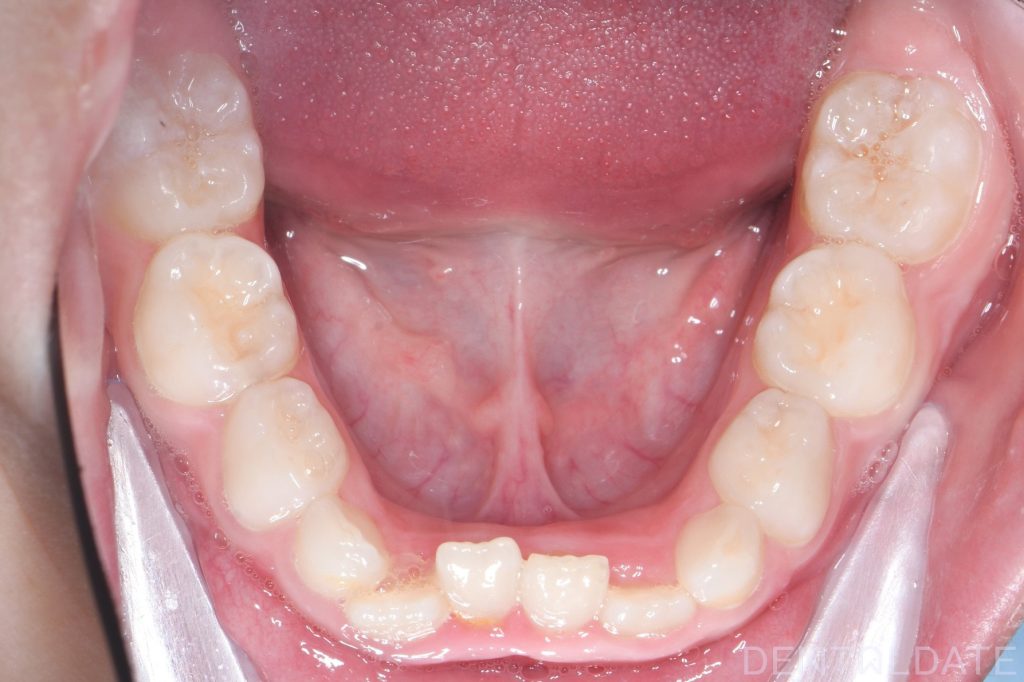

Parents sought an orthodontic consultation due to concerns about the aesthetics of their child’s smile.

To achieve harmony between function and aesthetics, a Haas appliance was used, followed by a myofunctional appliance.

We continue to monitor the young patient’s growth and development.